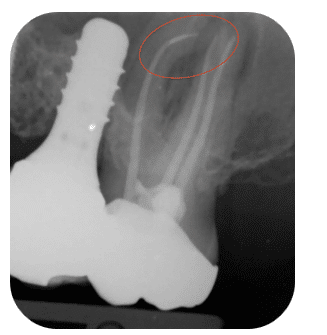

- Location (coronal / middle / apical third)

| Location | Coronal > Middle third | Apical third | Apical fragments block disinfection and harbor bacteria. |

Sometimes the safest approach is not removing the fragment but bypassing it.

Bypass means sliding a small hand file beside the fragment until reaching working length.

Once the path is regained, the fragment becomes part of the obturation.